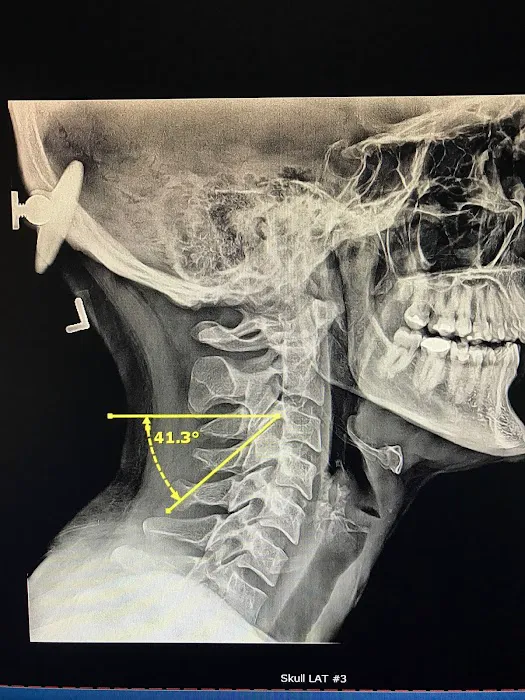

At Los Angeles Upper Cervical, the focus is on a unique and highly effective form of chiropractic care known as upper cervical chiropractic. This specialized approach centers on the crucial connection between the uppermost vertebrae of your spine (the atlas and axis) and your overall nervous system health. Misalignments in this delicate area can have far-reaching effects on your body, impacting everything from pain levels and mobility to neurological function and even your body's ability to heal itself. With a commitment to precision and a deep understanding of the body's intricate systems, Dr. Bello and his team offer a level of care that stands apart.

- Upper Cervical Chiropractic Adjustments: Precise, gentle adjustments focused on the atlas and axis vertebrae, aiming to correct misalignments that can impact the entire nervous system and body. These adjustments are often described as remarkably gentle yet profoundly effective.

- Detailed Scans and Diagnostics: Utilizing advanced imaging techniques to thoroughly assess the upper cervical spine and surrounding structures, guiding precise and effective treatment plans.

Jul 01, 2025 · Steve ImI came to see Dr Bello after a car accident last year. I was stiff and in a lot of pain. I wanted to make sure that if I saw someone after my accident they would know what they were doing and wouldn’t make me worse. Desperate for relief, I turned to Dr. Bello on a friend's recommendation. The accident affected my head, neck, back, hips, and threw off my jaw. His passion for upper cervical chiropractic care was evident from the start.Dr. Bello took detailed scans of my upper cervical vertebrae and head, which guided his treatment. He explained how neck displacements could impact the rest of my body. His targeted care began to alleviate my pain from day 1, including my jaw issues!! Nothing has ever helped my TMJ which was very much exacerbated atfter the accident.Beyond his chiropractic expertise, Dr. Bello collaborated with other practitioners. In the same building, I received acupuncture from Jessica at LaLuz Wellness, which helped with chronic pain and soft tissue injuries and trauma symptoms from the accident. Additionally, Jon Haupers LENS neurofeedback at Neurobalance addressed my TBI.This combination of treatments worked wonders. My pain lessened, my mobility improved, and I started to feel like myself again. Dr. Bello’s holistic approach, along with Jessica's and Jon's treatments, provided a comprehensive recovery plan.I would wholeheartedly recommend Dr. Bello . His genuine care, expertise, and dedication, combined with the collaborative efforts of his team, have made a profound difference in my life. I am incredibly grateful for their support and the thorough approach that has led to my healing.

Aug 16, 2024 · Heidi IreneI’ve been seeing Dr. Bello since January and I can’t say enough how much he has helped me. Prior to January, I was having horrible jaw pain that would last throughout the day and made eating a miserable experience. He did a 3D scan that showed the problem was actually my neck and explained how long it would take for it to improve with his adjustments.At first, I had to visit him twice a week because my neck was in such bad shape, but now I only have to see him once every three weeks and my neck muscles have gotten stronger and stabilized a lot. Still have a ways to go but I’m beyond happy with how these 7 months of care have gone.